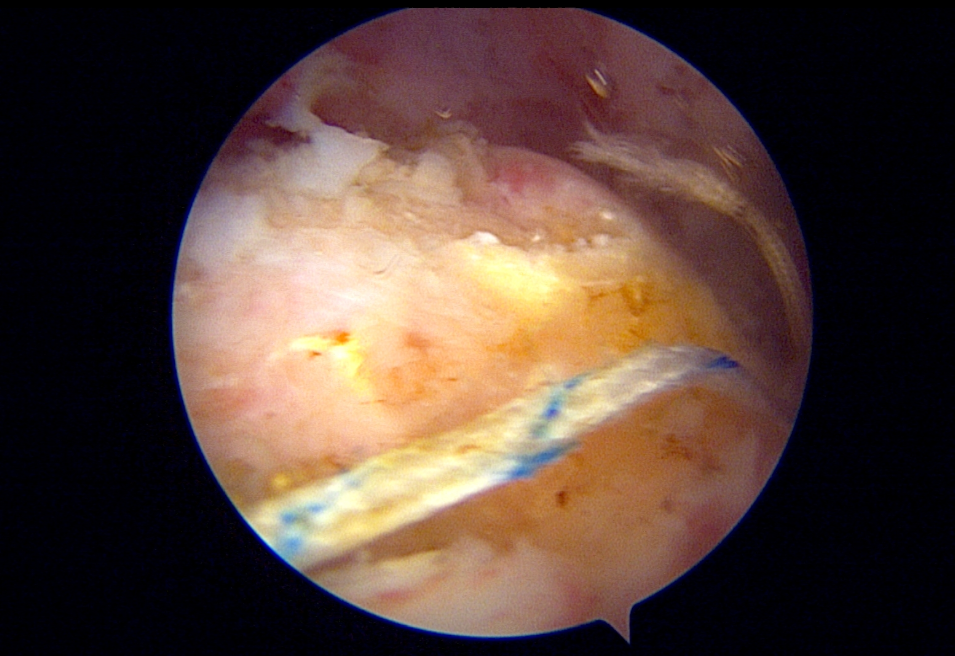

Artroskopi Yardımlı Latissimus Dorsi Tendon Transferi (LDTT)

Masif onarılamaz rotator manşet yırtıklarında (MIRCT) uygulanan latissimus dorsi tendon transferi tekniği. Sırt kasının tendonu omuz bölgesine transfer edilerek kaybedilen omuz fonksiyonu yeniden kazandırılmaktadır.

Artroskopik görüntü — tendon geçişi